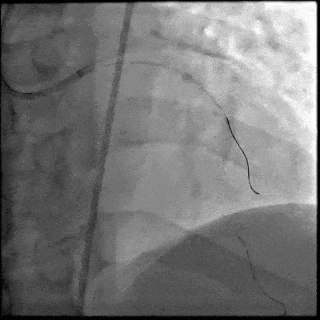

5月28日8:00,葛均波院士团队在中山医院16号楼16楼中伟厅成功连线喀什二院导管室,沪喀远程手术正式开始。8:35,新疆喀什二院导管室内股动脉入路通路建立后,行左右冠脉造影示左前降支中段存在85%的严重狭窄,狭窄位于血管分叉路口且紧邻心肌桥;且左回旋支中段近乎闭塞,血管细窄且迂曲,病变弥漫。8:59,葛院士于上海操控血管介入机器人主端,将指引导管送至左冠脉开口,并操控主支导丝和分支血管保护导丝通过狭窄病变,后送至前降支和对角支血管远端以建立轨道,同时利用介入机器人的微速调整功能避开心肌桥,以亚毫米级精准定位释放1枚支架。在成功处理患者左前降支病变后,葛院士通过搓捻机械操纵杆,远程精细调整导丝“进攻”方向,顺利通过左回旋支次全闭塞病变。因血管相对细小且病变弥漫,葛院士决定采用单纯球囊扩张术处理,即刻造影提示几乎无残余狭窄,避免了额外的支架植入。10:10,撤出所有导丝及导管,手术顺利结束。

【DSA图4.治疗结束造影】